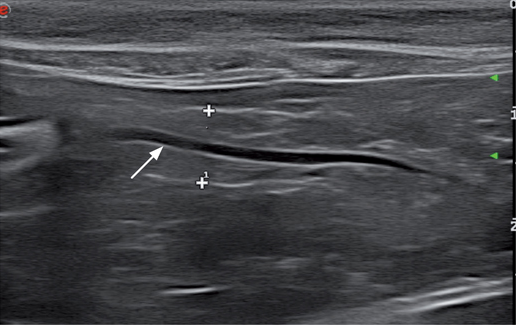

急性胰腺炎,慢性胰腺炎及无任何胰腺炎症状的老年猫都可见胰管扩张,所以超声影像发现胰管扩张不能作为诊断胰腺炎的指征(图14)。胰管扩张也可见于结石性疾病。此外,胰腺炎造成的总胆管扩张,最后可能会导致胆囊扩张。